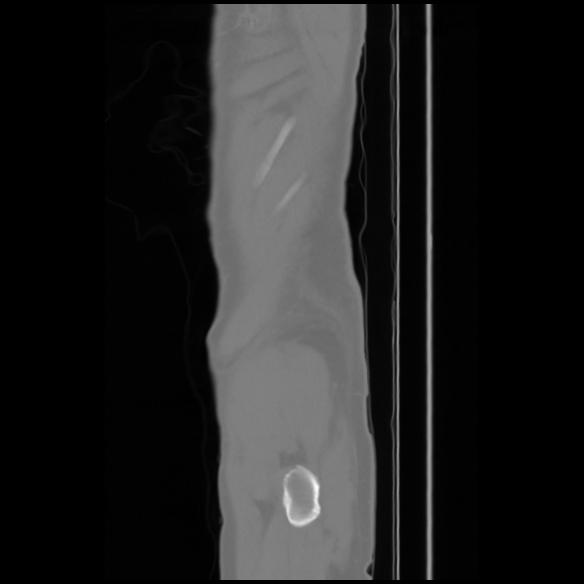

7 CUERPO,CE,Sagittal,3.000,CUERPO,Sagittal,